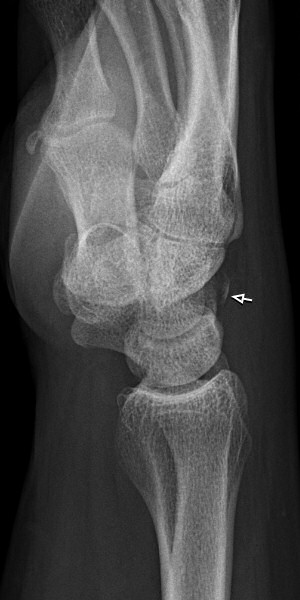

Skada: Fraktur triquetrium

- Dorsal slitfraktur (vanlig fraktur)

- Korpusfraktur

Odislocerad fraktur i korpus, behandlades med dorsal gipsskena i 4 veckor.